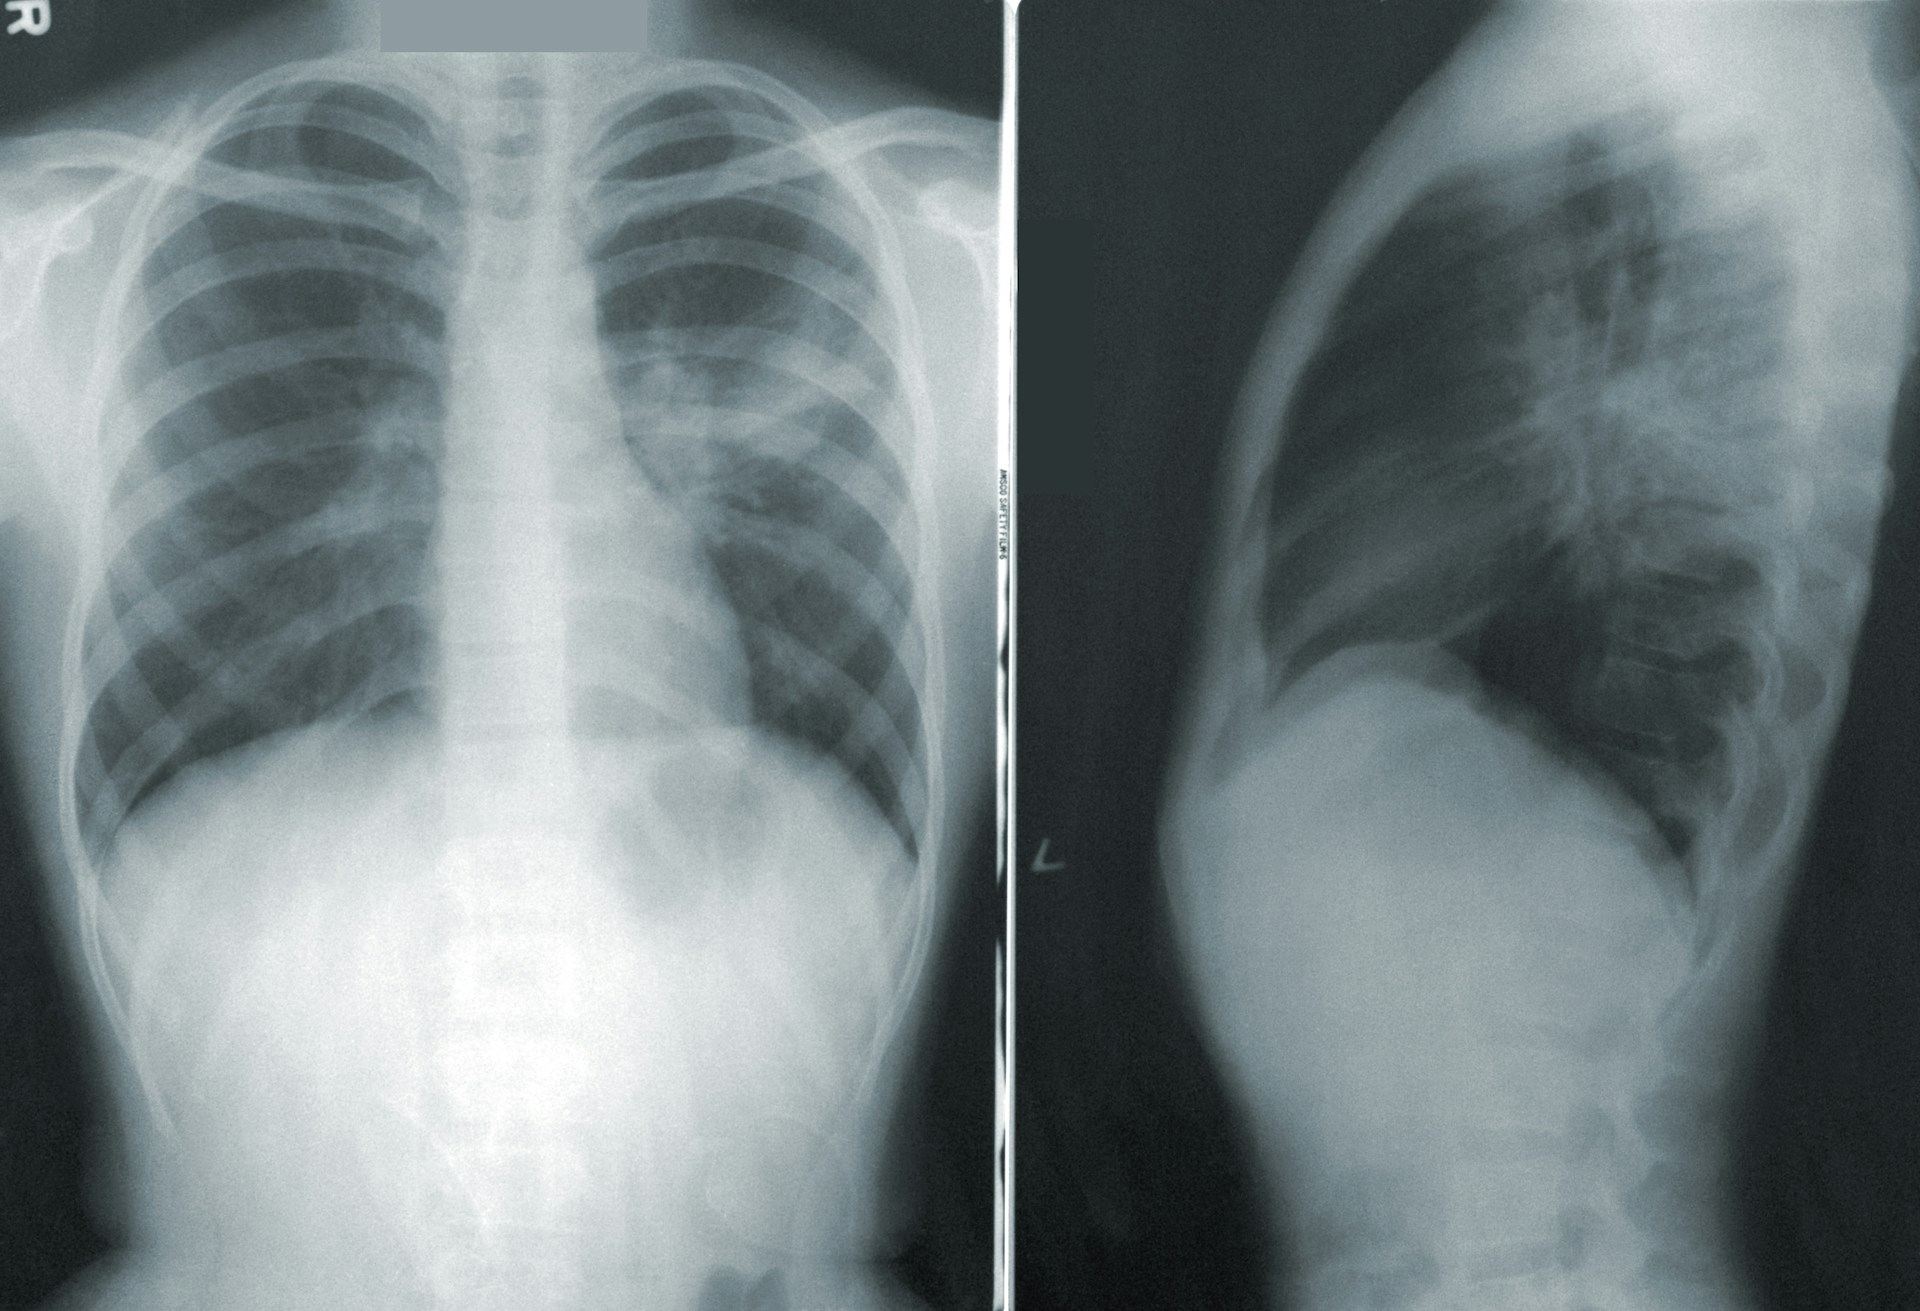

El examen que se suele realizar de forma preventiva es la tomografía computarizada. Esta se suele ofrecer a pacientes adultos mayores que fumaron por varios años o que dejaron de fumar en los últimos 15 años.